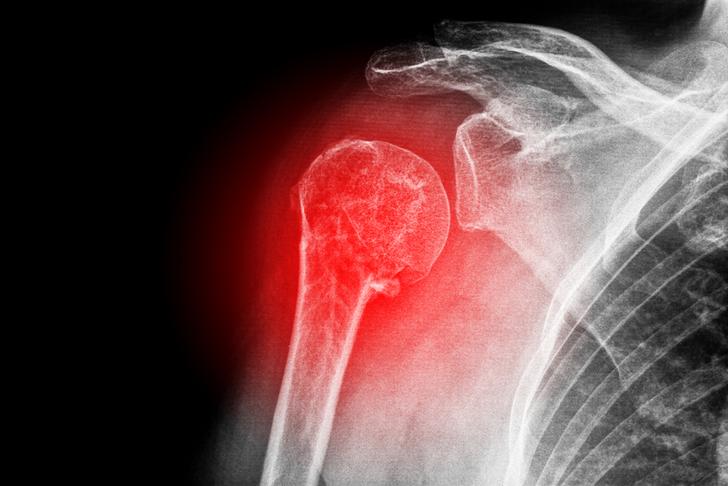

Fractures of the Proximal Humerus

A fracture of the proximal humerus, the upper part of the arm bone, can cause severe shoulder pain, swelling, and bruising [[8]]. These fractures often result from falls, sports injuries, or motor vehicle accidents.

Shoulder Dislocation

A shoulder dislocation occurs when the head of the humerus pops out of the shoulder socket [[9]]. This can cause intense pain, swelling, and an inability to move the shoulder. Dislocations can result from trauma, such as a fall or a sports injury, and can also occur due to joint instability.